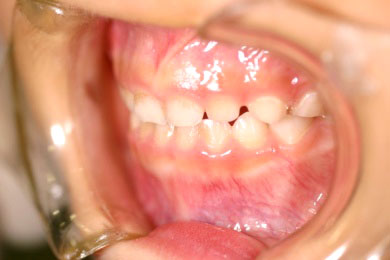

乳歯の反対咬合(下顎前突)を矯正して正常な上下関係に矯正した症例

Before

After

日本橋りゅうデンタルクリニックの子供の矯正歯科治療例です。子供の場合、なるべく早い時期に不正咬合を見つけて矯正歯科治療を開始してあげるべきです。このことによって、顎顔面の成長発育が正常に行われていきます。

年齢 5歳

治療期間 8ヶ月

治療費用 600,000円

治療のリスク 患者様が装置を使用しないと治りません